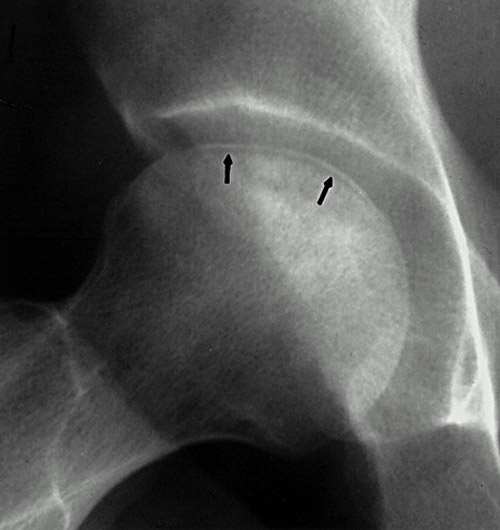

Возможно сомнения в диагностике связаны с нетипичной рентгенологической картиной. На снимке большая киста, которая расположена в центре головки, а при АВН начинается в верхней нагрузочной зоне. Отсутствует коллапс, сохранилась сферичность головки; не очень выраженный, но характерный признак "Crescent Sign".

Диффернциальную диагностику надо делать с доброкачественной кистой или метастазами. Но двухсторенная киста встречается очень редко, и киста в шейке распологается более дистально, чем при АВН. Гетерогенная картина головки немного напоминает метастаз, но без первичной опухоли и затяжной характер течения заболевания снимает подозрение на злокачественный процесс.

При наличии коллапса диагноз устанавить очень легко. Сканирование с изотопами тоже хороший метод исследования, который покажет "холодные" участки, окруженные "теплыми" зонами. Исследование в 25% дает погрешность, и поэтому на сегодня МРТ является "золотым стандартом" исследования. Пункция не помешает, но мне кажется, что здесь по классификации Ficat преколлапсный, т.е. вторая степень АВН.